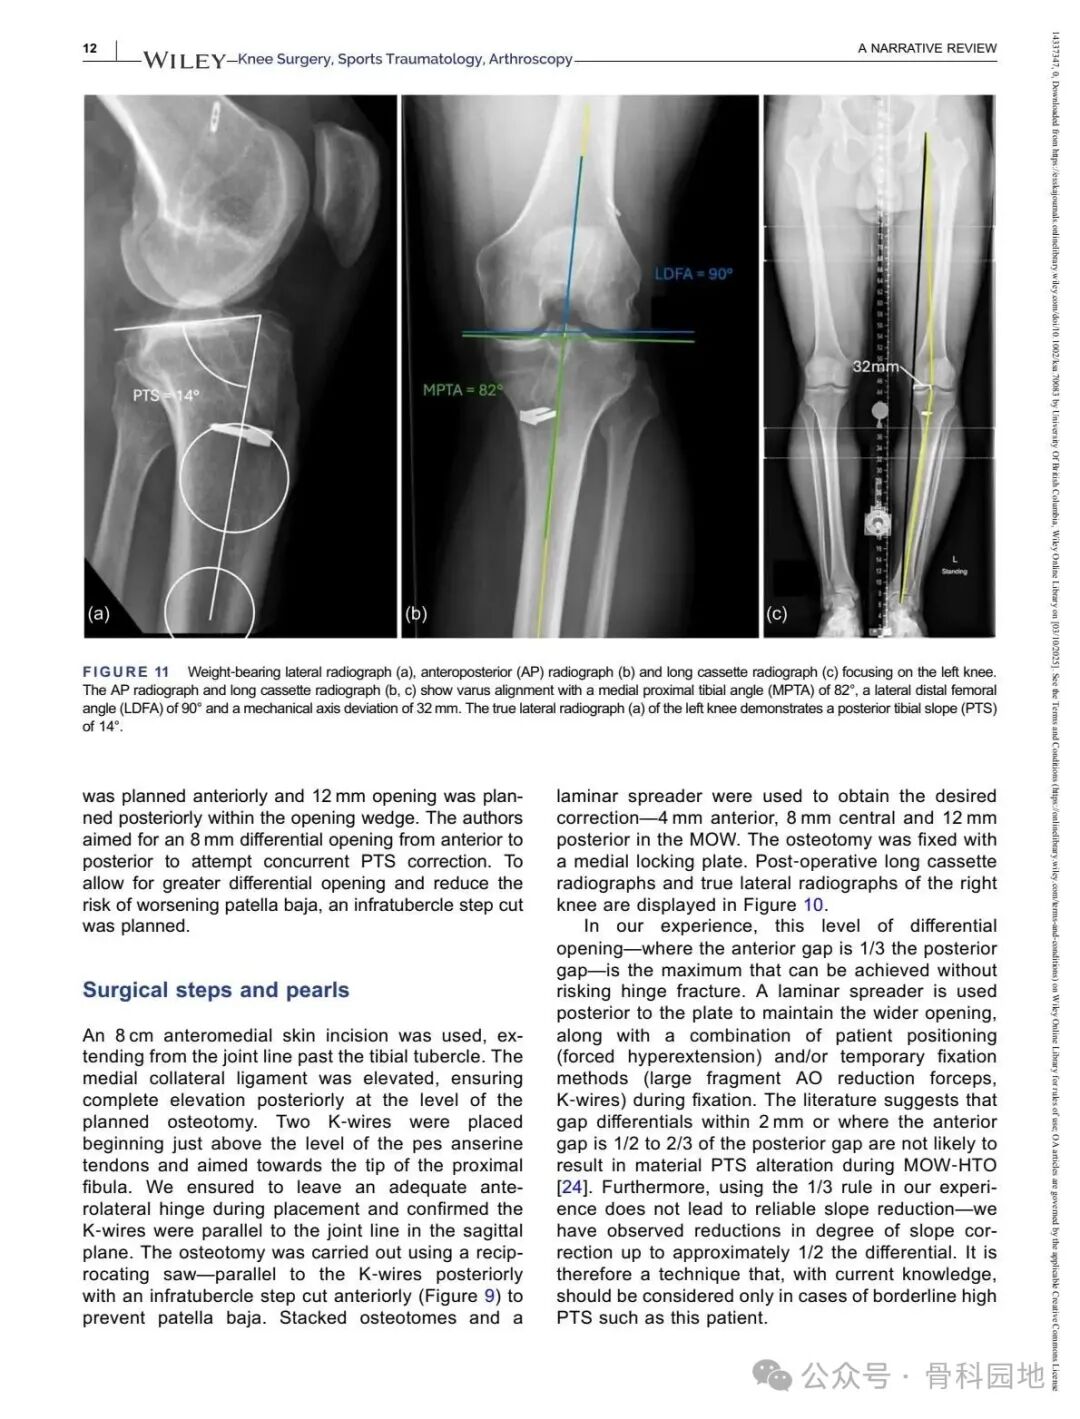

Although conventional high tibial osteotomy (HTO) primarily addresses coronal plane malalignment, the importance of sagittal plane alignment—specifically the posterior tibial slope (PTS)—cannot be overlooked in the setting of cruciate ligament insufficiency. Combined coronal and sagittal plane deformities are relatively rare and present unique surgical challenges. This narrative review summarizes the available literature and presents technical tips for managing complex biplanar deformities through a case‑based discussion of different techniques.